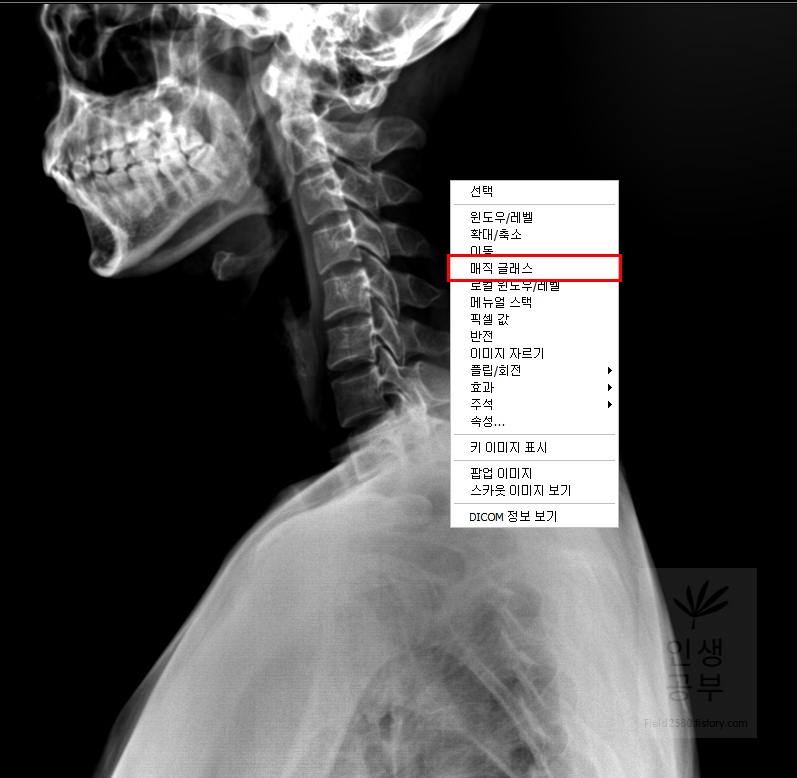

돋보기 화면에 ±가 있는 버튼을 이용해서 화면 전체의 크기를 조절할 수 있는 반면에 부분적인 부분만 확대할 수 있는 방법이 있습니다. 바로 매직 글래스메뉴를 이용해서 부분적인 확대 버튼을 이용하실 수 있습니다. 또한 부분적인 확대 화면 안에서도 추가적인 확대와 축소를 이용할 수 있습니다.

X-ray화면 창에서 마우스 오른쪽 버튼을 클릭해 줍니다. 그 후에 매직 글래스라고 적힌 항목을 선택해줍니다.

부분적으로 확대해서 보고 싶은 X-ray화면에 마우스 왼쪽을 클릭해서 확대해줍니다. 부분적으로 네모칸이 생기면서 선택한 부분을 조금더 크게 보여주는 창이 생깁니다.

만약에 조금 더 크게 보고 싶다면 마우스 왼쪽을 누른 상태에서 Ctrl을 누른 후에 11시 방향이나 12시 혹은 1시 방향으로 올려주면 매직 글래스 화면 내에 부분적으로 확대된 X-ray 화면이 더 커집니다.

다시 축소하고 싶다면 마우스 왼쪽을 누른 상태에서 Ctrl을 누른 후에 4시 6시 혹은 8시 방향으로 내려주면 매직 글래스 안에서 부분적으로 확대된 X-ray 화면을 줄일 수 있습니다.